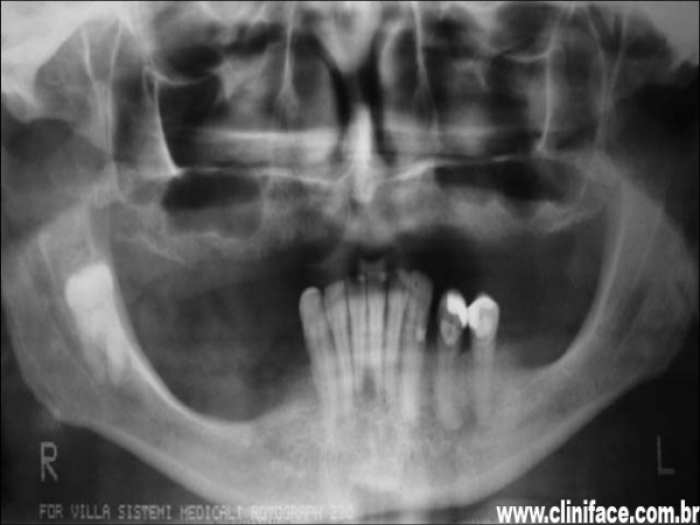

Raio X inicial